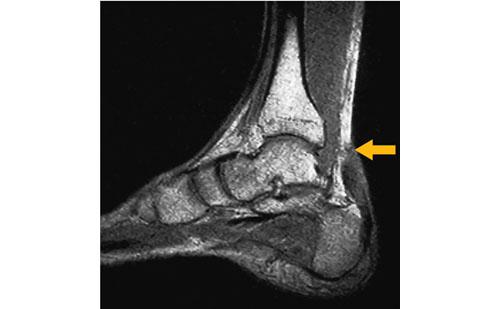

14

理学療法士実地問題 -

第52回 午前

重要度:標準

39歳の男性。野球の試合中にジャンプしてボールをキャッチした着地時に、踵に疼痛と違和感とを訴えた。その直後から歩行困難となったために、応急処置の後に緊急搬送された。搬送先の病院で撮影された足部MRIを示す。矢印は損傷部位を示す。受傷直後の処置として適切なのはどれか。

1

足底板による固定

2

足関節周辺の保温

3

足関節底屈位での固定

4

強擦法による下腿部のマッサージ

5

端座位による下腿下垂位での安静